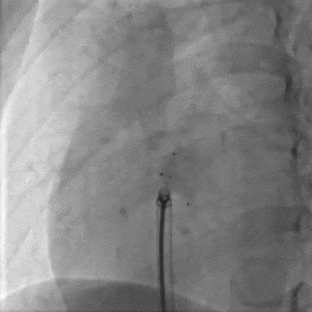

术式入径:采取DSA+经胸超声引导经皮介入的方式。

送入输送系统

沿导丝送入输送鞘

左盘展开

DSA下牵拉成型线使左盘成型,超声可见左盘后撤贴靠房间隔

右盘展开

随后固定钢缆不动,回退鞘管,右盘展开

成型锁定

封堵器双盘扣合住间隔,鞘管抵住封堵器,前顶钢缆。助手固定钢缆和鞘管,牵拉成型线锁定

DSA可见Mark点聚集到一起,多普勒显示即刻阻流效果良好

DSA下可见封堵器整体移动,右盘面未被拉开

DSA下可见Mark点聚拢